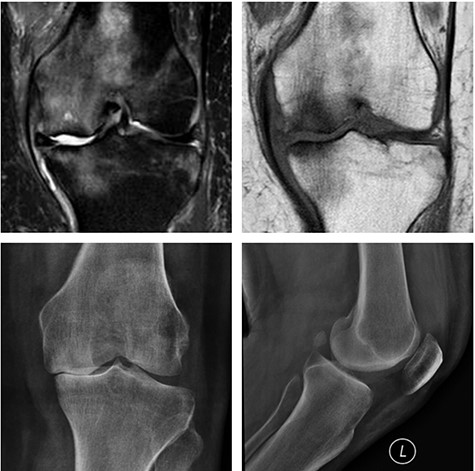

Left knee T2 coronal MRI (top left) showing MP and femoral condyle SIFK with articular failure of both surfaces; Top right: same image (T1); Bottom left: orthostatic anterior view X-ray image of the same patient showing medial compartment bone-on-bone contact; Bottom right: lateral view X-ray image of the same patient.